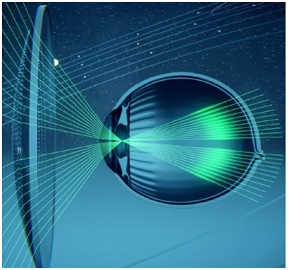

На второй схеме представлено миопическое глазное яблоко: по мере роста длины глаза миопия прогрессирует, и зрение вдаль становится все более нечетким.

При ношении ребёнком обычных линз, световой сигнал фокусируется перед сетчаткой и частично уходит в периферийную зону, которую специалисты называют «мнимым пространством».

В такой ситуации глазное яблоко рефлекторно реагирует на световые сигналы и слегка вытягивается за ними, удлиняется. При миопии это грозит увеличением «минуса» в диоптриях ваших линз.